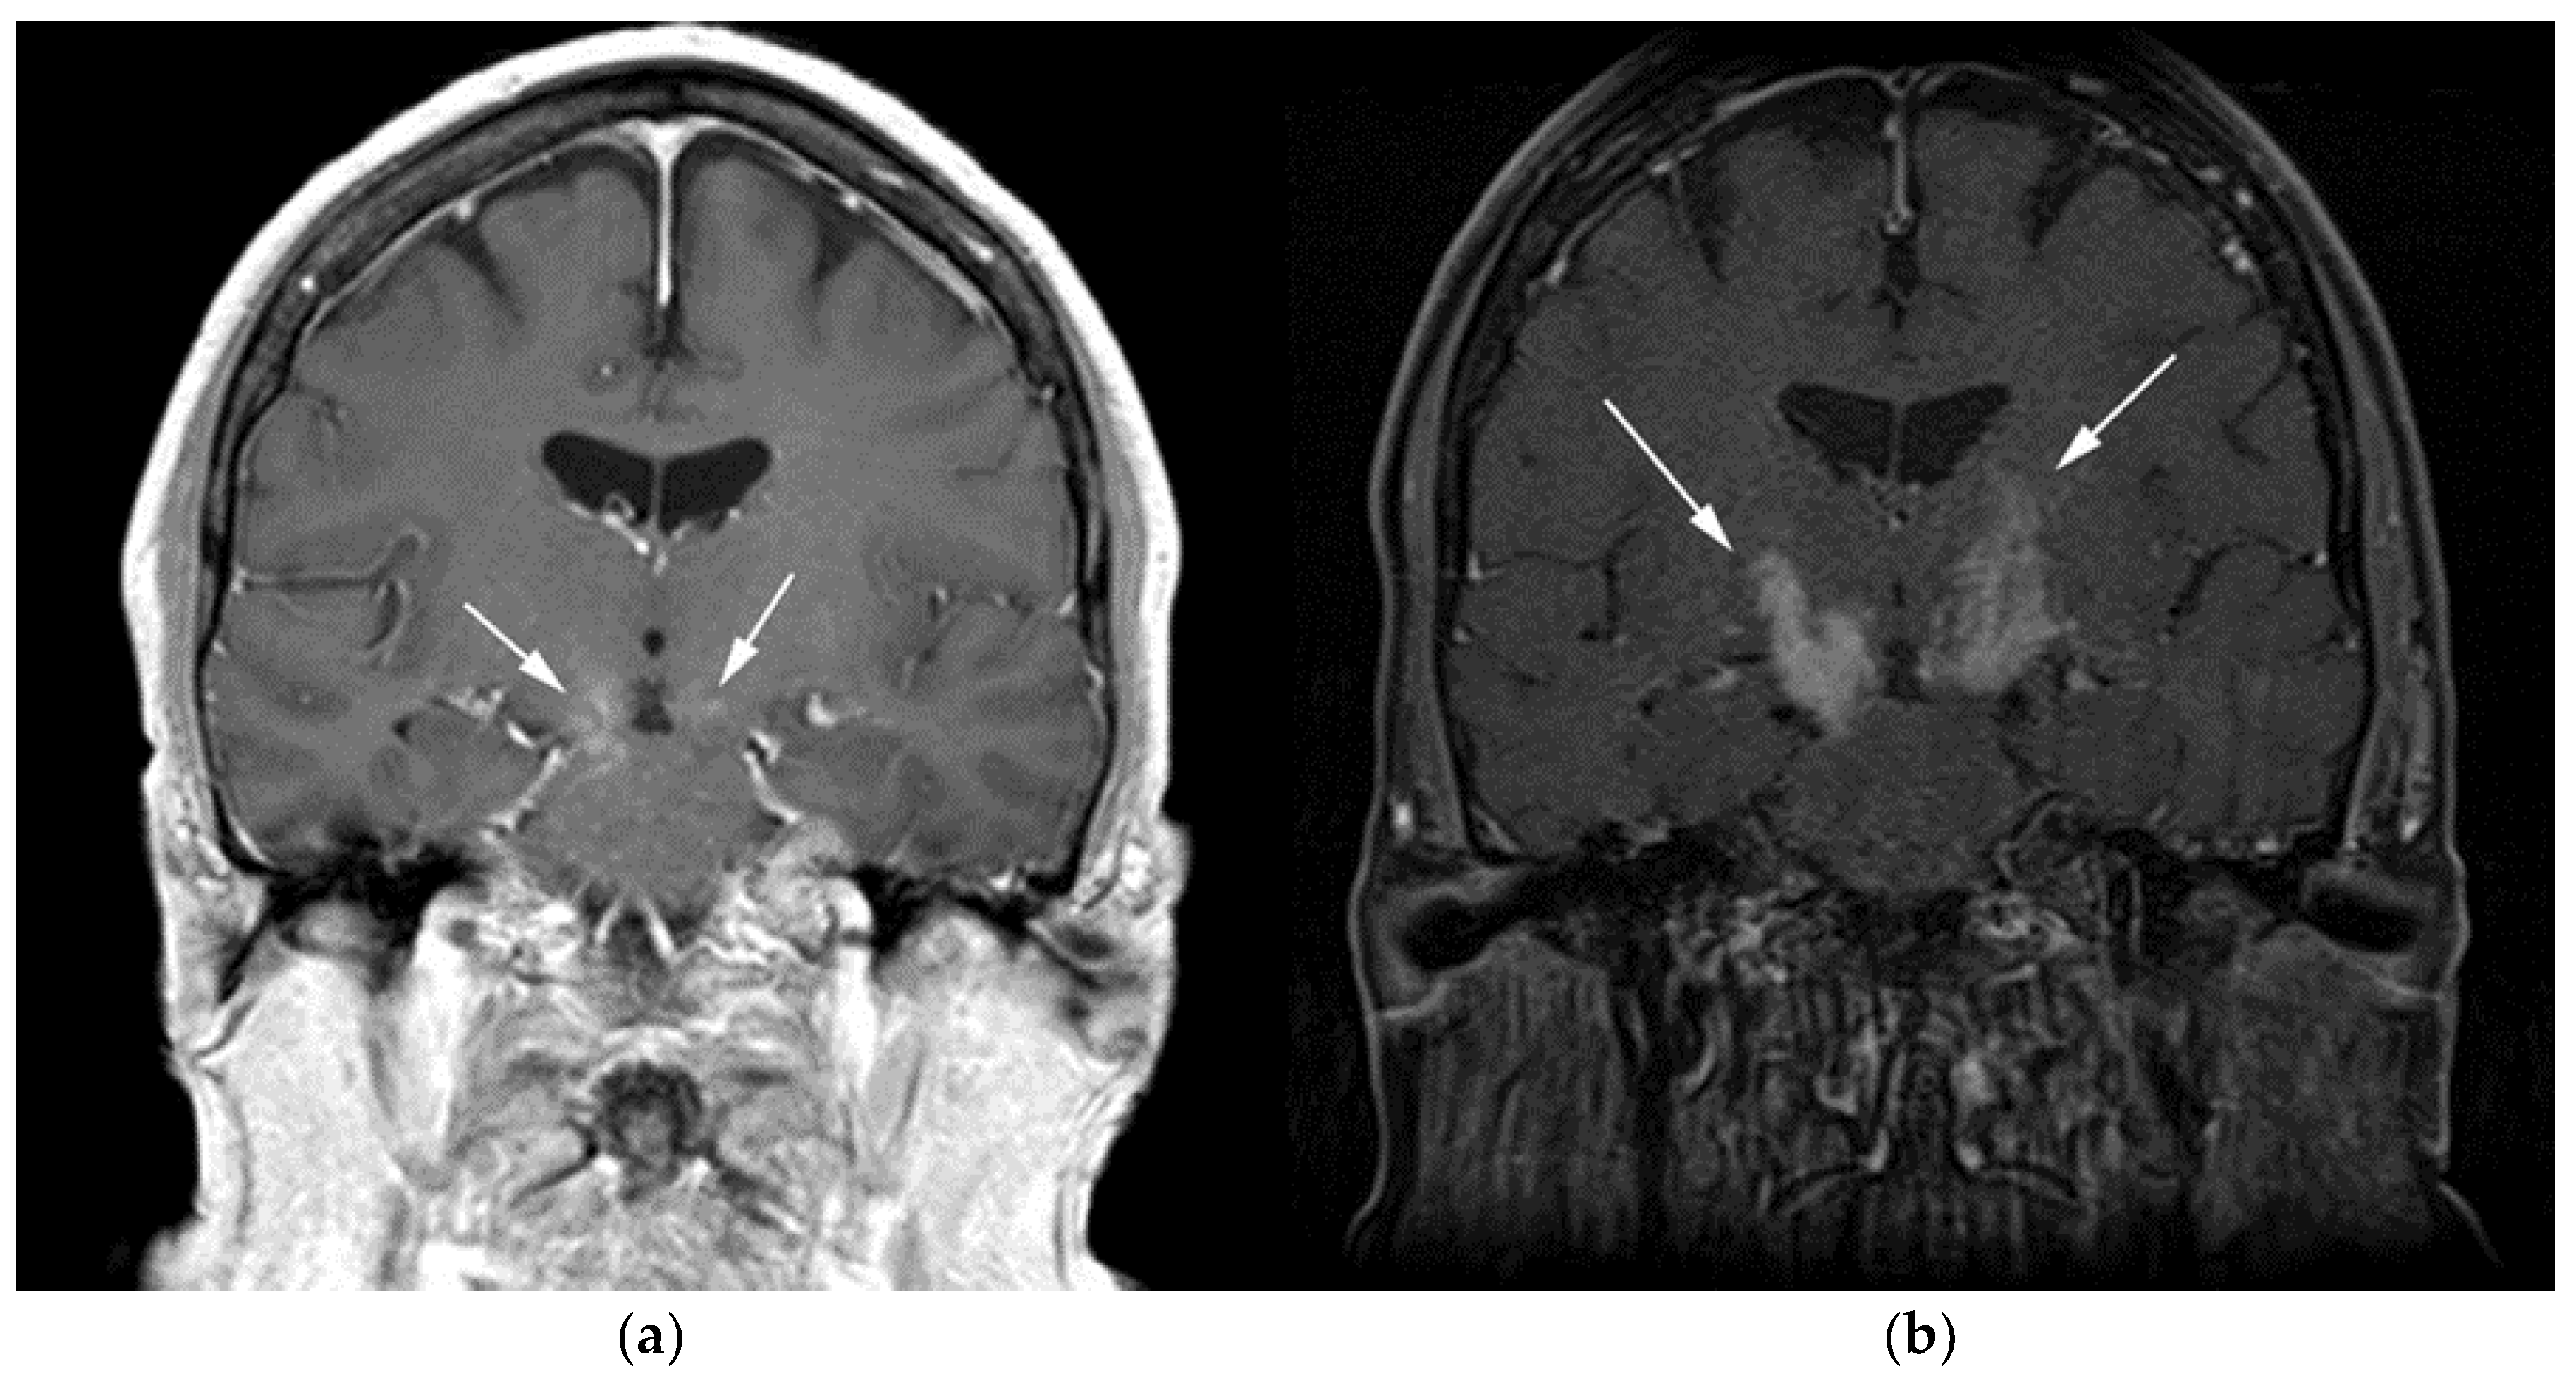

Figure 2.

A 64-year-old-woman presenting with rapid onset of memory deterioration and altered sensorium. (a) Coronal MRI T1 post-contrast images show subtle enhancement along bilateral deep nuclei. At this time, no diagnosis was determined. After 3 weeks, patient presented to emergency department with worsening symptoms. A follow-up MRI was performed. (b) Coronal MRI post-contrast fat-saturated images revealed progressive increase in extent of diffuse infiltrative enhancing masses (white arrows).

Figure 3.

Same MRI series. (a) Axial post-contrast MRI image shows lesions extending caudally to involve the bilateral superior cerebral peduncles and anterior aspect of the mid-brain. (b) Axial MRI T1 post-contrast fat-saturated images show involvement of the posterior limb of the internal capsule and the thalami bilaterally (white arrows). (c) Extension along the lateral aspect of the pons, dentate nucleus, and the middle cerebellar peduncles (white arrows). (d) Axial FDG fused PET/CT image shows increased activity in the aforementioned lesions. Additional hypermetabolic lesions are seen along the course of the corticospinal tract (white arrows). Imaging findings and pattern of involvement are consistent with lymphomatosis cerebri. (e) H&E section shows a tumor composed of large and pleomorphic cells with intermingled small lymphocytes. Primacy CNS lymphoma typically demonstrates an angio-centric predilection. (Original magnification 400×, H&E stain). Other differential diagnoses include a vasculitic process, toxic or metabolic encephalopathy, paraneoplastic syndrome, or acute disseminated encephalomyelitis. Biopsy showed a large non-cohesive B-cell lymphocyte population consistent with LC.

Special sequences such as apparent diffusion coefficient (ADC) maps help differentiate PCNSL from high-grade tumors such as glioblastoma multiforme (GBM). PCNSL demonstrates marked diffusion restriction on diffusion-weighted images (DWI) with lower ADC values compared to GBM due to tumor restriction in lymphoma cells. The main role of 18F-FDG PET/CT in CNS lymphoma is to differentiate PCNSL vs. disseminated systemic lymphoma involving the CNS [14]. Additionally, 18F-FDG PET/CT can help in distinguishing PCNSL from mimicking disorders such as hypometabolic intracranial opportunistic infections including CNS toxoplasmosis [15,16,17,18]. Imaging findings of LC include diffuse, non-mass-like lesions within both hemispheres involving the white matter, corticospinal tracts (CST), and deep gray matter. These lesions show patchy contrast enhancement and diffuse abnormal T2W hyperintensity. Unlike PCNSL, LC shows variable restriction on DWI [19]. Regions commonly affected in LC include the subcortical, deep, and periventricular white matter, CST, U-fibers, corpus callosum, and gray matter, with less frequent involvement of the spinal cord compared to PCNSL [12]. Contiguous spread of lesions from the cerebral white matter to the brain stem along the corticospinal tract (CST) is a notable feature of LC, which can involve both the brain and brain stem (Figure 2 and Figure 3). Unlike PCNSL, the characteristic neuroradiological findings of LC with 18F-FDG PET/CT have not yet been established; nevertheless, they are usually seen as hypermetabolic mass like lesions [8,20]. MRI spectroscopy (MRS) may help differentiate LC from other neurodegenerative or inflammatory conditions. On MRS, evidence of high cell membrane turnover (high choline peak), neuronal damage (decreased NAA levels), high lactate levels, and elevated lipids is typically demonstrated. Although many of these MRS features resemble high-grade gliomas and metastases, elevated lipids have been shown to be potentially useful to differentiate between these entities and LC [21]. The diagnosis of lymphomatosis cerebri should be considered in patients presenting with a rapidly progressive decline in cognitive function, dementia, or behavioral abnormalities. Imaging findings including diffuse bilateral hemispheric cortical spinal tract involvement and pathology may show predominant infiltration of the neuronal tracts without the formation of definite masses. It is crucial that diagnosis of LC is only made after the exclusion of other common etiologies as the clinical and imaging findings of LC can be misattributed to other diffuse infiltrative brain tumors, leukoencephalopathy, vasculopathy, degenerative disease, ischemic processes, infectious processes, and toxic demyelinating diseases in addition to dementias and other psychiatric disorders such as depression [8,12].